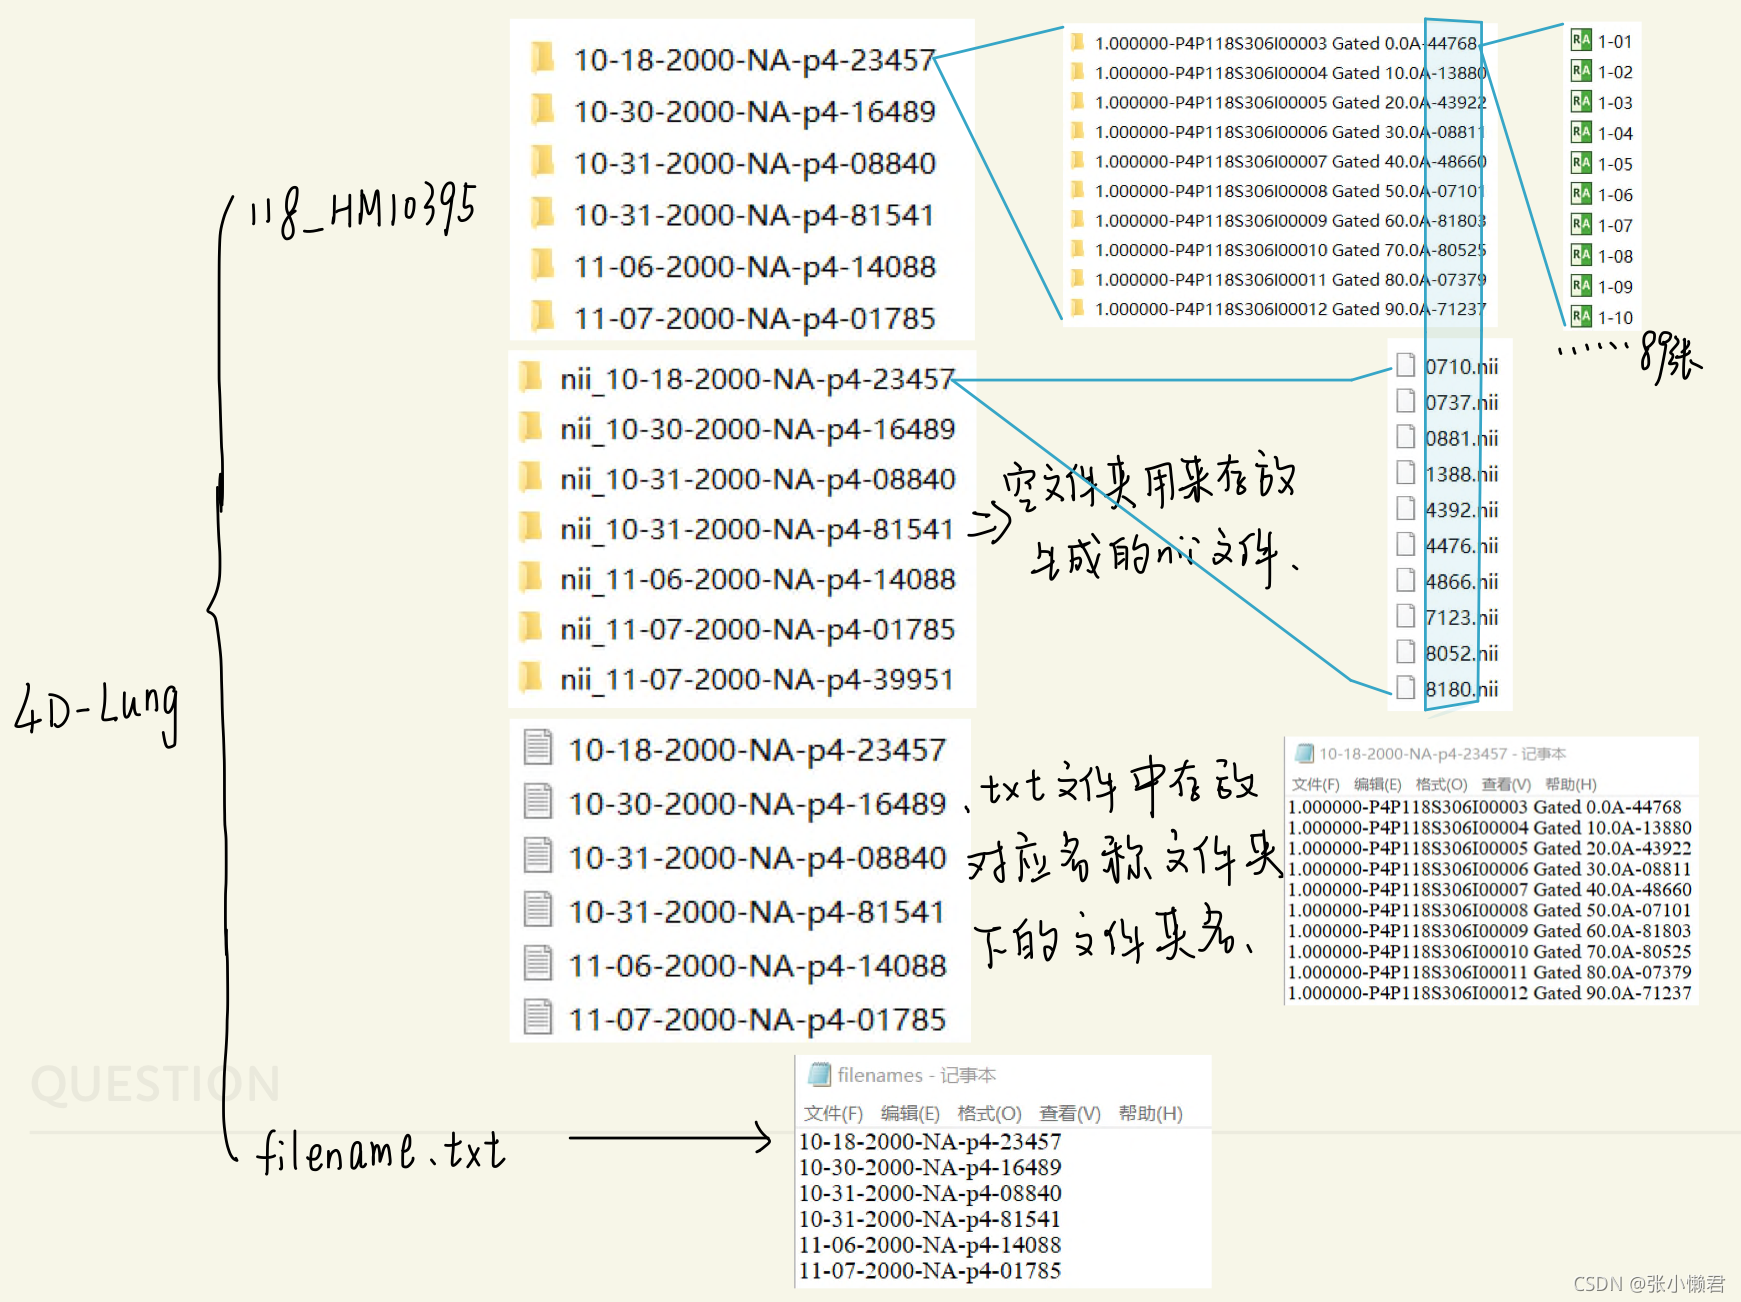

(3)批量DICOM转批量nii

DICOM2nii.py文件存放在118_HM10395文件夹下

#DICOM2nii.py

import dicom2nifti

import os

pathRoot = 'E:\\PostGraduate\\NBIA\\CBCT_Lung\\118\\manifest-1632732569283\\4D-Lung' #当前程序所在文件夹

pathNow = 'E:\\PostGraduate\\NBIA\\CBCT_Lung\\118\\manifest-1632732569283\\4D-Lung\\118_HM10395'

#将filename.txt文件中的文本都赋给列表filenames[]

os.chdir(pathRoot) #进入filename.txt的所在目录4D-Lung

filenames = []

for line in open("filenames.txt"): #从filenames.txt文件中读取行信息

filenames.append(line.rstrip()) #.rstrip去除掉文本文件中的换行符

for i in range(len(filenames)):

os.chdir(pathNow)

Daughternames = []

Renames = []

txt_name = filenames[i] + '.txt'

#print(txt_name)

for line in open(txt_name): # 从Daughtername.txt文件中读取行信息

Daughternames.append(line.rstrip())

Renames.append(line.rstrip()[-5:-1])

for j in range(len(Daughternames)):

os.chdir(pathNow + '\\' + 'nii_' + filenames[i])

Dicom_ID = pathNow + '\\' + filenames[i] + '\\' + Daughternames[j]

Nii_ID = Renames[j]

dicom2nifti.dicom_series_to_nifti(Dicom_ID, Nii_ID, reorient_nifti=True)最后深度学习网络使用的数据集,有JPG格式的也有nii格式的,但可能nii格式可能会比较方便处理一些,因为一个nii格式数据包含了一个病人一次检查的所有切片图像,而同一个病人的JPG图片可能就需要80多甚至更多的JPG文件。